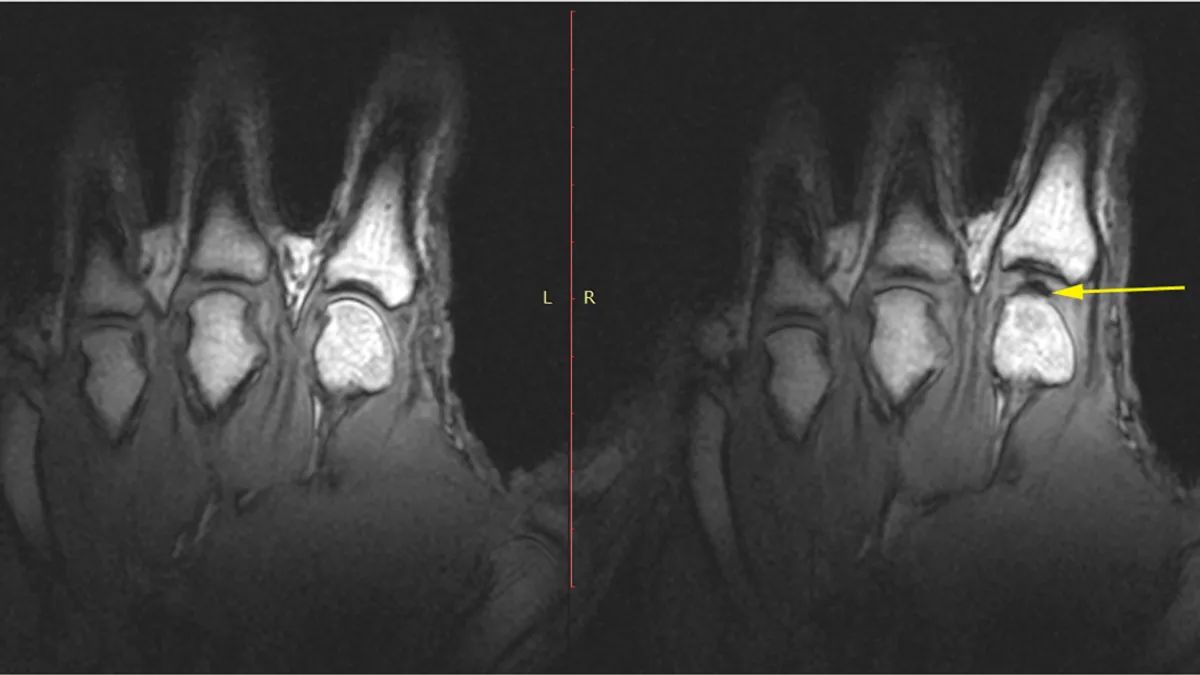

В дослідженні 2015 року вчені дослідили суглоби пальців пацієнта на апараті МРТ. Довгий час вважалося, що тріск є результатом крихітної газової бульбашки, яка буцімто згортається в рідині довкола суглобів. Але це не так, йдеться в дослідженні МРТ.

Натомість вчені побачили, що під час тріскотіння суглоба пальця насправді утворюється газова порожнина там, де її раніше не було. Коли людина починає розтягувати суглоб, там утворюється простір, схожий на вакуум, заповнений газом. Саме вона видає звук тріску.